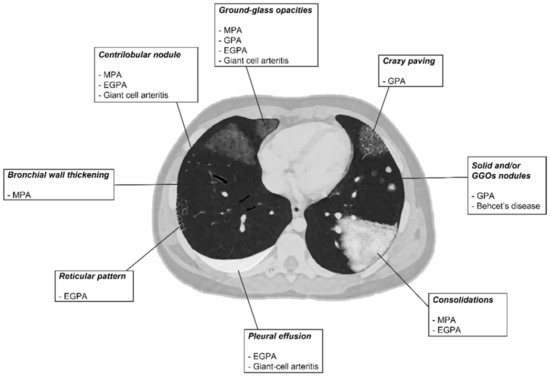

2.2. Radiological Features

| Vasculitis | HRCT Features |

|---|---|

| MPA | GGOs due to hemorrhagic alveolitis (common); consolidation, nodules with centrilobular distribution (less common) |

| GPA | Solid nodules, GGOs due to hemorrhagic alveolitis (common); halo sign, crazy paving (less common) |

| EGPA | Migrant GGOs, transient consolidation, irregular bronchial wall thickening, small nodules with peribronchial and centrilobular distribution, pleural effusion. |

| Takayasu arteritis | Stenosis and/or occlusion of segmental arteries; stenosis and/or occlusion of lobular or main pulmonary arteries (less common); C.E. of vessel wall may be evident |

| Giant-cell arteritis | Aneurism or dissection of the thoracic aorta (common); nodules, GGOs, monolateral or bilateral pleural effusion (less common) |

| Bechet’s disease | Subpleural alveolar infiltrates and wedge-shaped or ill-defined rounded areas with increased opacity, pulmonary artery aneurism |